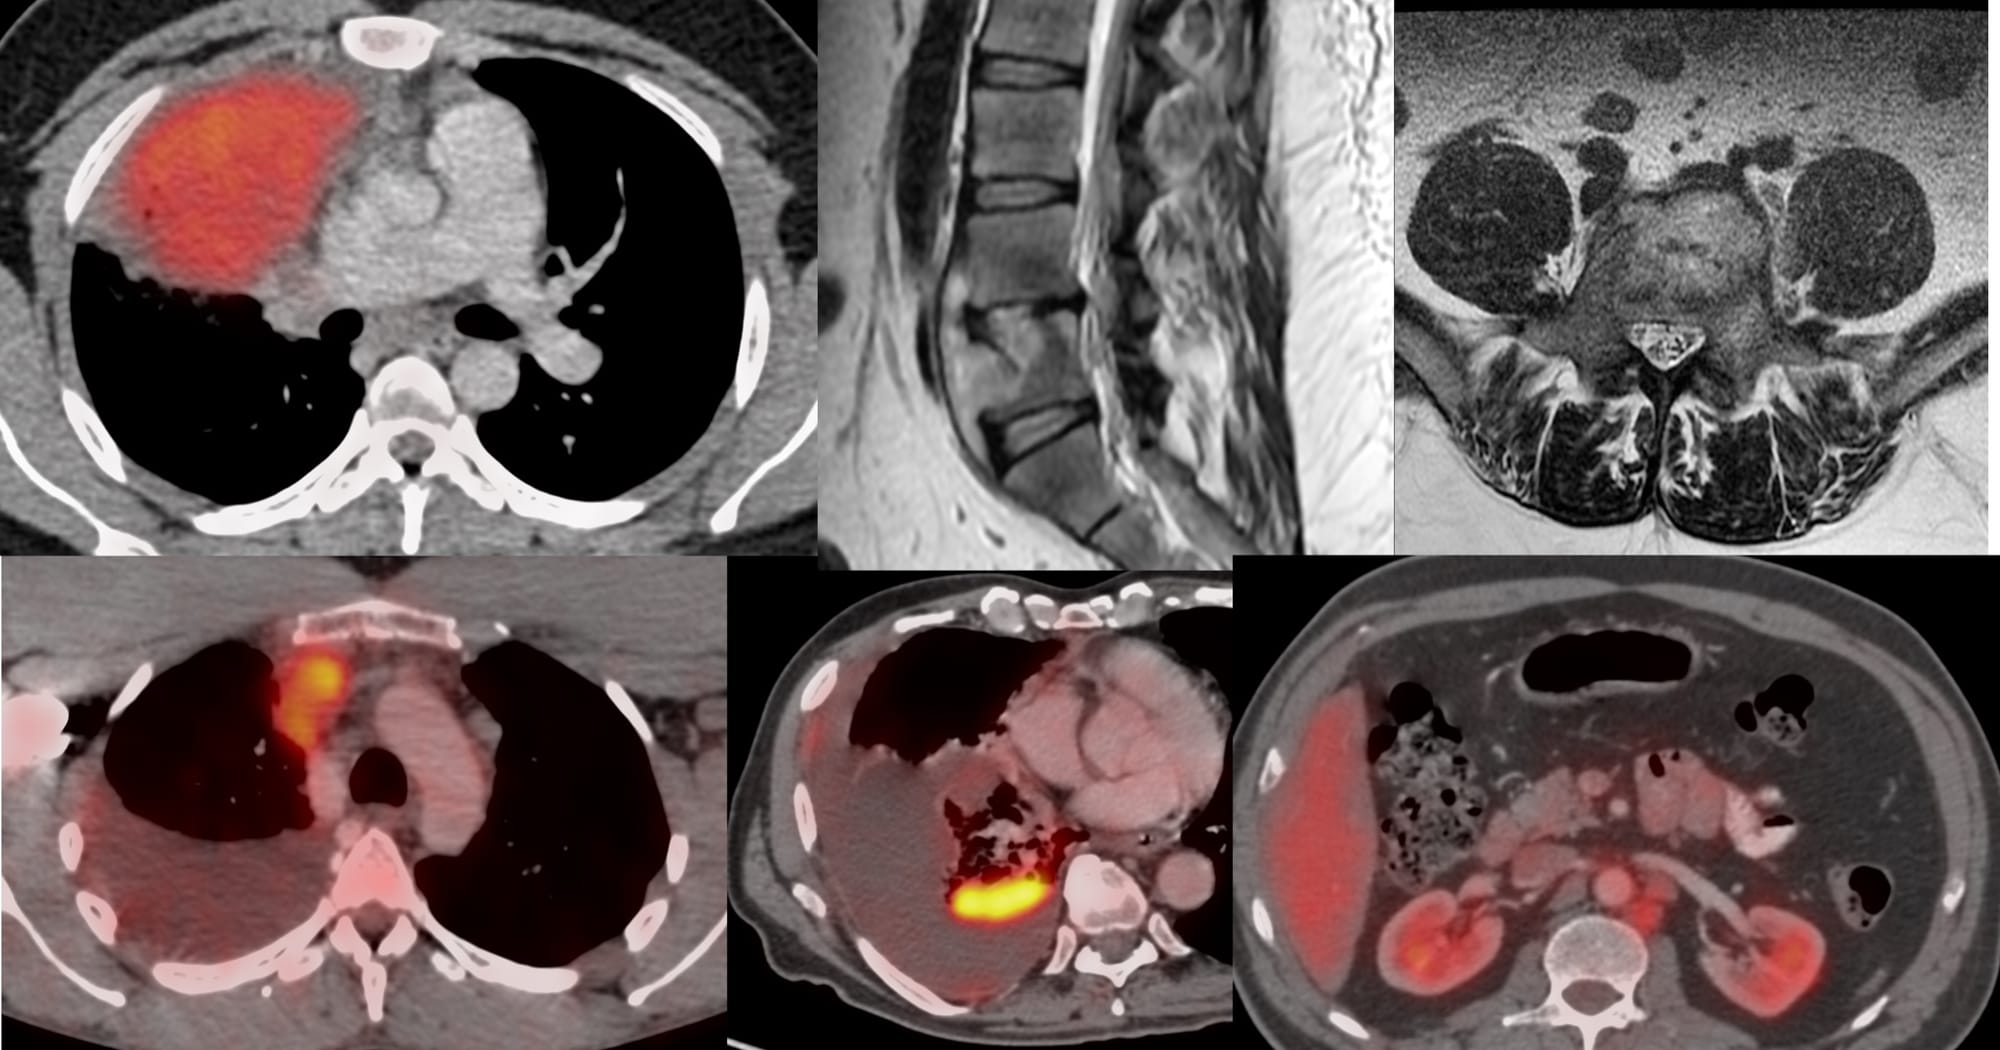

Lecture - CT Guided Spine Biopsies

Lecture - Pulmonary Interventions

Case of the Day 100 - 2025 09 10 - T2 Dark Thoracic Spinal Vertebral Lesion - Transpedicular Biopsy